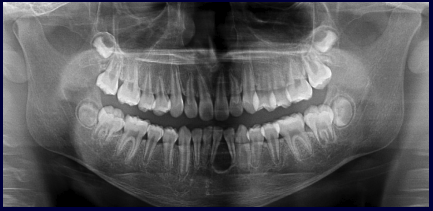

What are the 7 signs of IAN involvement?

1.Darkening of the roots 2.Interruption of the white line 3.Diversion of the mandibular canal 4.Deflection of the roots 5.Narrowing of the roots 6.Dark and bifid roots 7.Narrowing of mandibular canal

What is the most important part of pre-implant assessment?

7-10 mm of crestal bone need to be available to withstand stresses.

What is important to understand about the alveolar ridge for implants?

When teeth are lost, the ridge is lost. Furthermore, maxillary sinuses into remaining alveolar bone. Disuse atrophy occurs even if well-fitting dentures are used.

What are the important aspects of assessment for mandibular implants?

1.Mandibular canal 2.Mental foramen 3.Anterior loop of mandibular canal 4.Incisive branch of IAN 5.Lingual canal in the midline